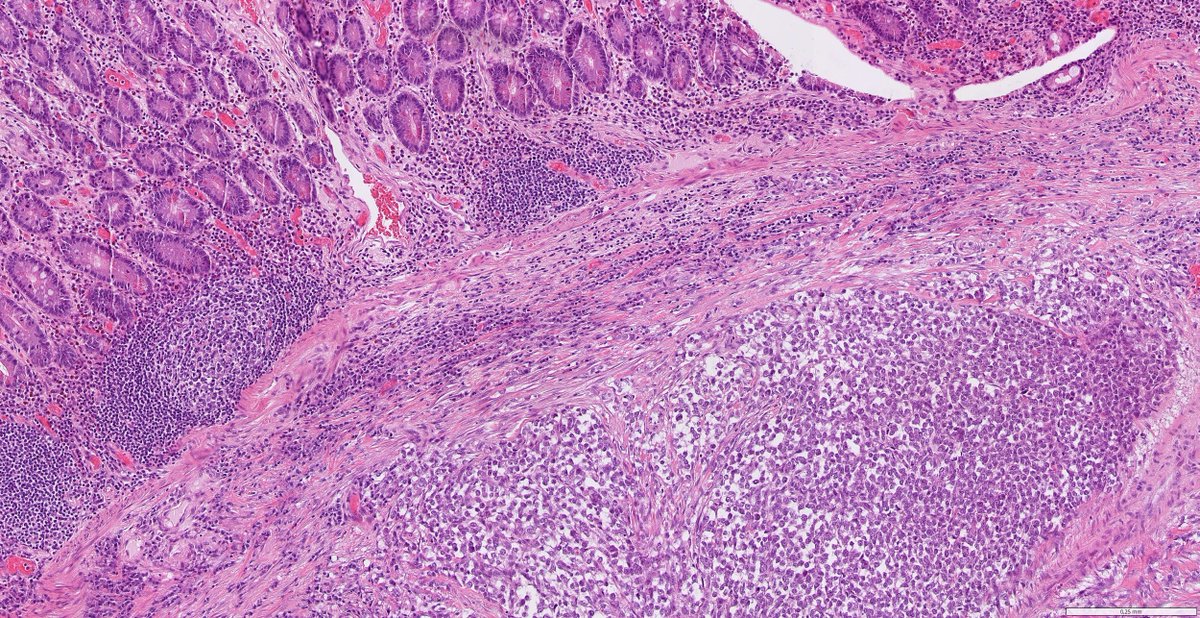

Not everything is what it seems. Middle-aged patient. Consult case. Minimal clinical data. Ileal resection for obstruction → tumor found. Let’s follow the diagnostic trail. Short thread, do the polls in order (and no sneak peek...)

Middle-aged patient. Consult case. Minimal clinical data. Ileal resection for obstruction → tumor found.

Let’s follow the diagnostic trail. Short thread, do the polls in order (and no sneak peek...)